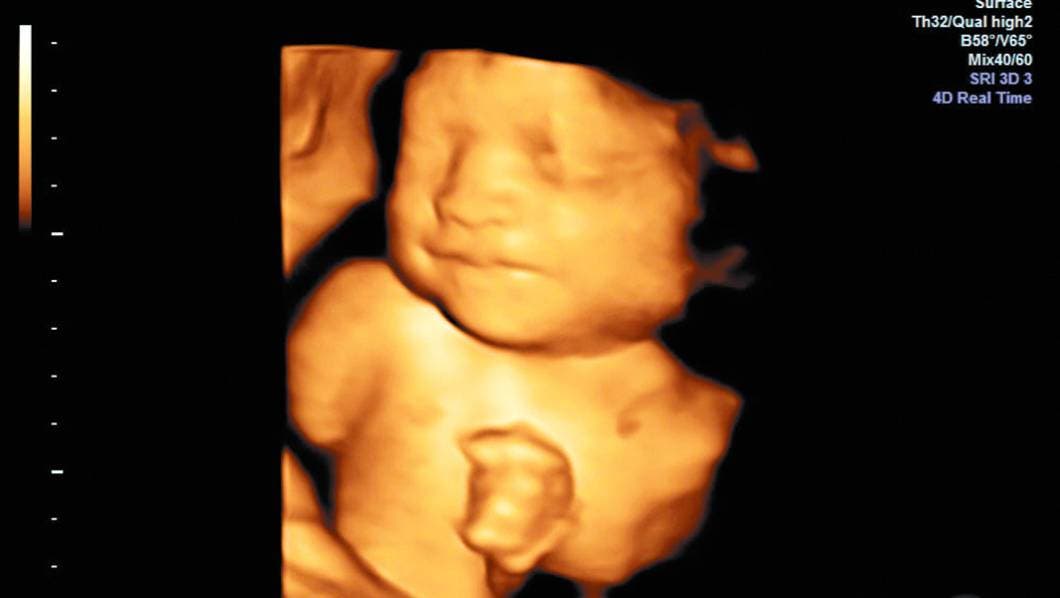

A detalle. El investigador busca que mediante software el ultrasonido detecte posibles riesgos de parto prematuro.